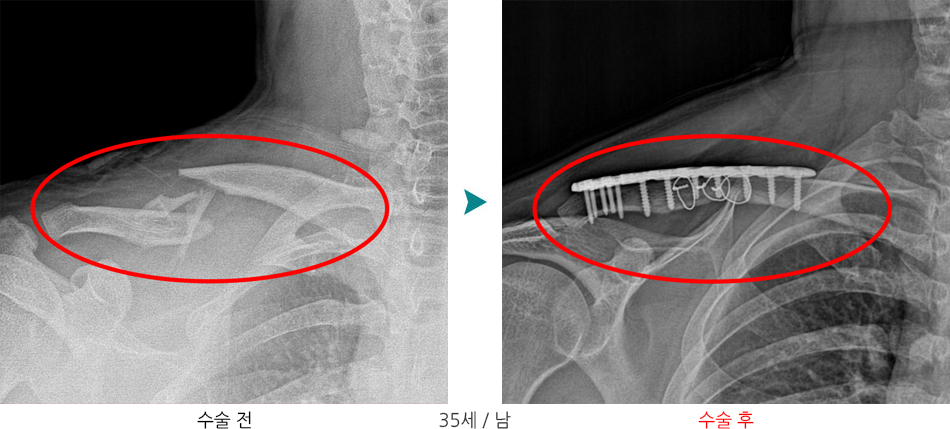

수술적 치료

- 개방적 정복술 및 내고정술(ORIF (open reduction and internal fixation))

개방적 정복술 및 내고정술